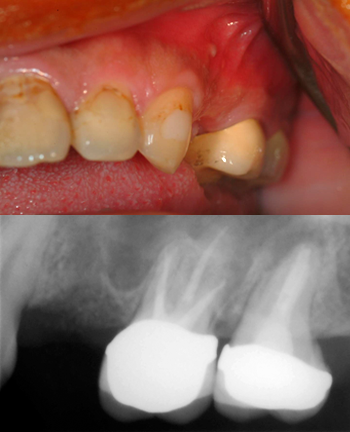

主訴: 我的牙齒有長膿包會痛

診斷: 右上顎側門齒根尖膿瘍及上顎四顆門齒齲齒

治療: 蛀牙太嚴重無法保留門齒,拔牙及補骨粉,兩顆植牙在兩側門齒以支撐作四顆門牙牙橋,患者又能有燦爛笑容